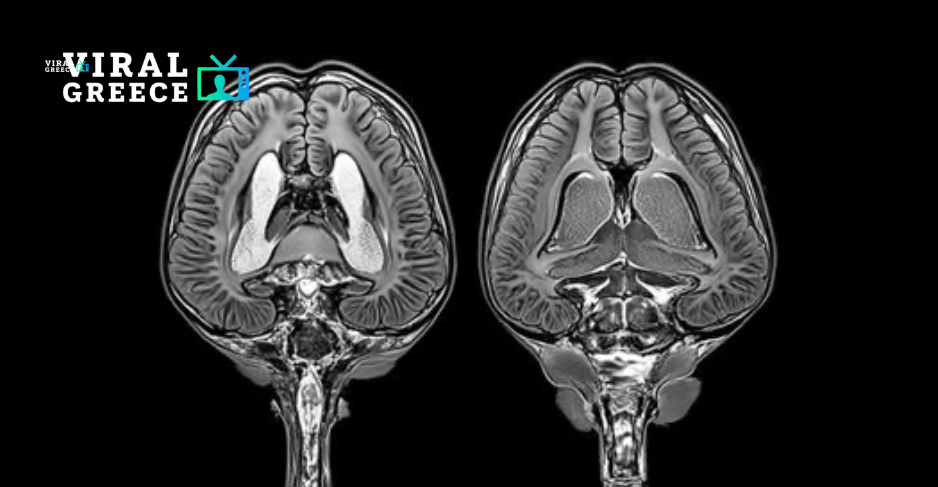

Μια νέα έρευνα αποκαλύπτει μια ανησυχητική σύνδεση ανάμεσα στη χρόνια στέρηση ύπνου και στη μακροχρόνια βλάβη του εγκεφάλου.

Επιστήμονες που μελέτησαν ποντίκια με ελλιπή ύπνο διαπίστωσαν ότι η παρατεταμένη αϋπνία οδηγεί τα ανοσοκύτταρα του εγκεφάλου—τα αστροκύτταρα και τη μικρογλία—σε υπερδραστηριότητα.

Τα αστροκύτταρα, τα οποία συνήθως απομακρύνουν τις περιττές συνάψεις, άρχισαν να καταστρέφουν περισσότερες εγκεφαλικές συνδέσεις και κυτταρικά υπολείμματα. Παράλληλα, η μικρογλία, που είναι υπεύθυνη για την απομάκρυνση κατεστραμμένων κυττάρων, εμφάνισε αυξημένη δραστηριότητα.

Αν και αυτές οι διεργασίες μπορεί αρχικά να έχουν προστατευτικό ρόλο, η υπερδιέγερση των συγκεκριμένων κυττάρων έχει συνδεθεί με νευροεκφυλιστικές παθήσεις, όπως η νόσος Αλτσχάιμερ.